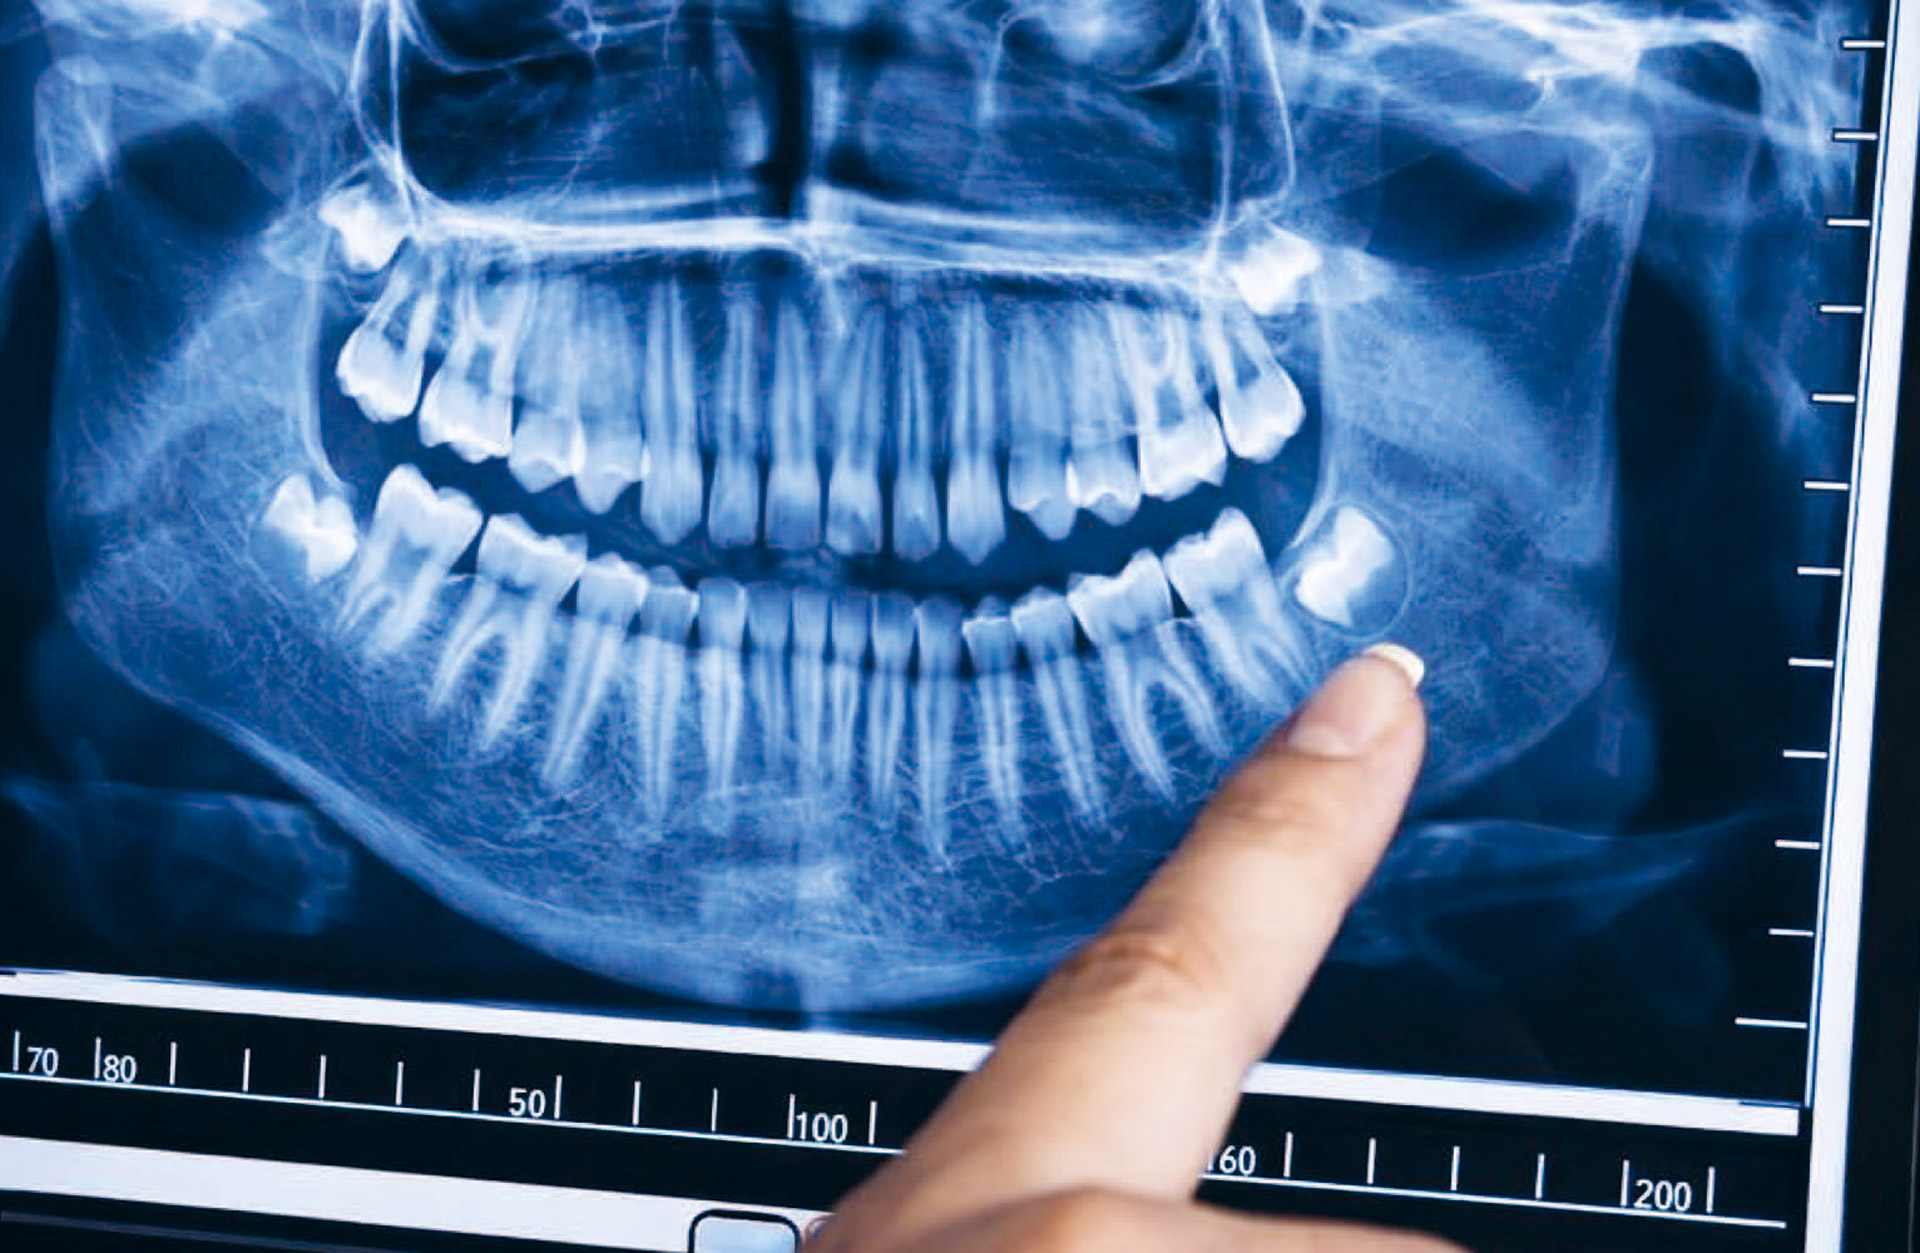

Figure 3. To determine whether an immigrant is a minor or an adult, third molars are useful.

Like dental development is staged, so is bone growth. The most used bones are those in the hand/wrist (figure 4). Like teeth these bones are graded according to an atlas [25]. Teeth and bone develop independently, consequently, it might be a good argument for using both dental and bone development. Research has demonstrated that there is a close correlation between bone and dental age [43]. If bone age and dental age is close it might also be close to chronological age, but if they differ one must look for a reason behind such difference.

Because of the wide variation in material and statistical method, different dental age estimations will give different answers when applied to the same material. It has been recommended to use more than one method, and some believe this would give a more accurate result. With the current knowledge it is more important to look at the background material which constituted the research material and the statistical approach (figure 3).